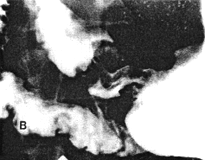

Case 29.3 V.D., 30 year old male, complained of epigastric pain not responding to antacids. Radiographic examination showed a gastric ulcer 1.5cm in diameter, on the lesser curvature at the angulus (Fig. 29.3A); no signs of malignancy were seen. Intially there was marked contraction of the pyloric sphincteric cylinder, which contained a few prominent mucosal folds; this was associated with delay in emptying of liquid barium. After barium had filled the cylinder, it was seen to remain contracted throughout the examination; although a minor degree of relaxation occurred occasionally, the apperances remained as illustrated most of the time, with absence of cyclical activity (Fig. 29.3B). Longitudinal mucosal folds were evident in the contracted cylinder. Endoscopic biopsy showed a benign looking gastric ulcer in the corpus. Microscopically there was mixed inflammatory cell infiltration, diagnosed as acute on chronic gastritis. No evidence of malignancy was seen. Repeat endoscopy 2 months later showed that the ulcer had healed.

| Fig. 29.3. A Case V.D. Gastric ulcer on lesser curvature at angulus (open arrow). Marked contraction of sphincteric cylinder (filled arrow). B Case V.D. Gastric ulcer at angulus (open arrow). Constant contraction of sphincteric cylinder (filled arrows) with absent cyclical activity. | B |